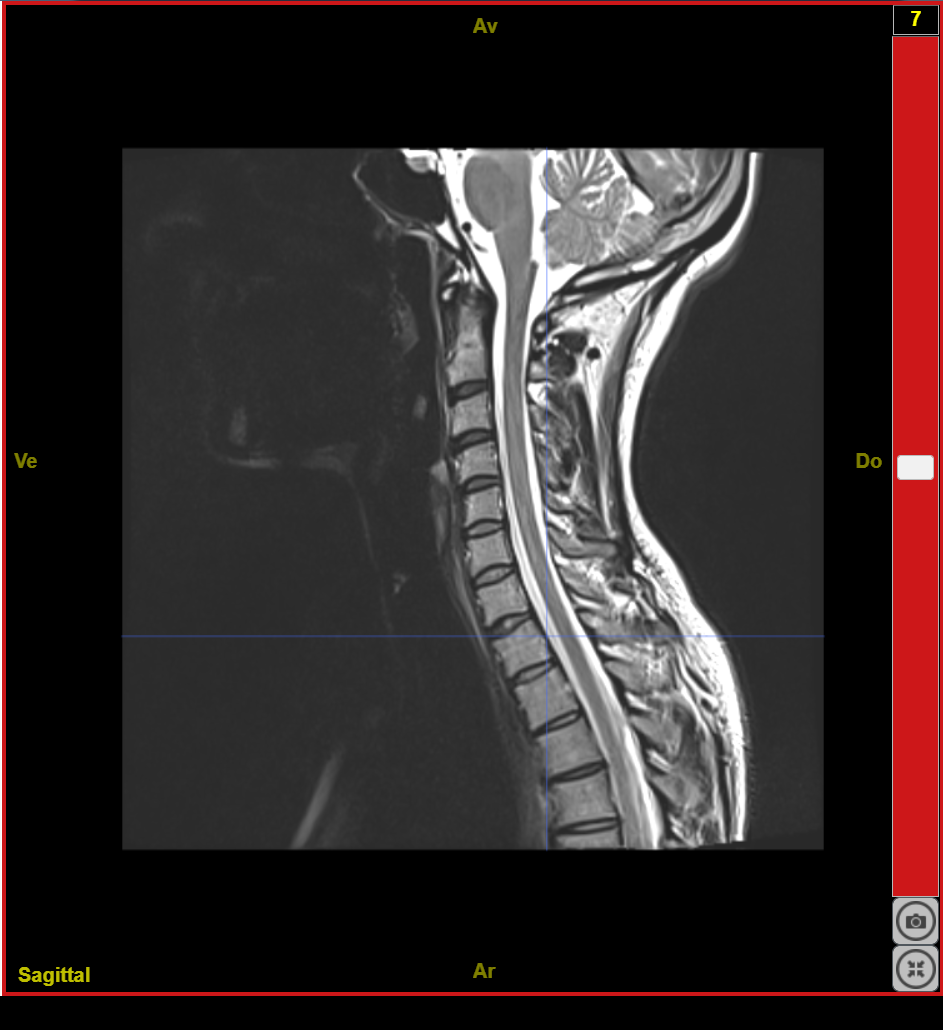

IRMsujet12131MoelleEpiniereSaineC1T5 T2